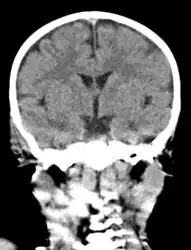

The diagnosis of mastoiditis is clinical—based on the medical history and physical examination. Imaging studies provide additional information; The standard method of diagnosis is via MRI scan although a CT scan is a common alternative as it gives a clearer and more useful image to see how close the damage may have gotten to the brain and facial nerves. Planar (2-D) X-rays are not as useful. If there is drainage, it is often sent for culture, although this will often be negative if the patient has begun taking antibiotics. Exploratory surgery is often used as a last resort method of diagnosis to see the mastoid and surrounding areas.[7][8]

Acute mastoiditis

CT scan: Otitis media (simple arrow) and mastoiditis (double arrow) of the right side (left side in image). The external auditory canal is partially occupied by suppuration (triple arrow). 44-year-old woman